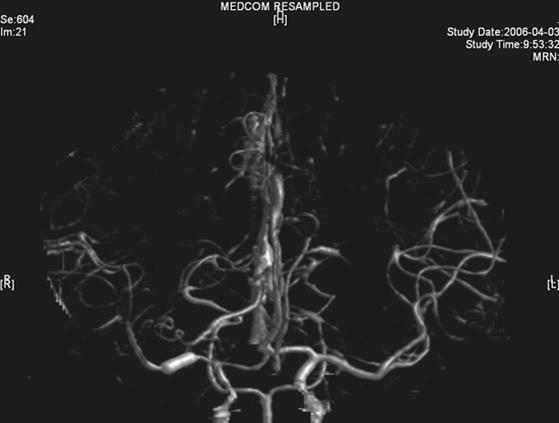

The same dose of aspirin, clopidogrel and subcutaneous LMWH was used after the operation. Two days after the stenting (Mar 23), three successive bouts of left limb weakness along with slight dizziness occurred, lasting about 10 minutes with intervals of 30 minutes. There were no abnormal signs between the first and second attacks. Babinski sign was noted during the second attack and persisted in the left between the second and third attacks with normal muscle strength, but she felt weakness. Blood pressure was 140/70 mmHg. After the third attack, her tongue deviated slightly to the left side. There was slight decrease in muscle strength and Babinski sign was positive in the left. Emergent CT displayed two low density lesions with clear edge and homogeneous density in the right basal ganglia (Figure 3). Aspirin 300mg was given emergently. Compared with the Transcranial Doppler (TCD) test before the operation (March 3), emergent TCD showed the blood flow velocity increased significantly in both anterior cerebral artery (ACA), especially in right ACA (Table 1). She got partial recovery after being given volume expansion treatment with low molecular dextran. Then she was given anticoagulant treatment with intravenous unfractionated heparin (UFH) (500 U/h). LMWH was stopped. On the next day, her muscle strength recovered to normal, but pathological sign persisted. Anticoagulation therapy was continued along with dual antiplatelet therapy. On Mar 25, limb weakness appeared again, muscle strength was Ⅳ grade in the left, both Babinski sign and Chaddock sign were positive. Volume expansion with low molecular dextran was ineffective, and the dose of UFH was increased to750 U/h. Two days later, muscle strength and plantar reflex recovered to normal. On Mar 27, CT scan revealed that the lesion did not change compared with the previous scan, and there was no new lesion. Dose of UFH was reduced to 500H/h. During treatment, blood coagulation test was performed for several times, PT was stabled at 14.1~15.5 sec, APTT at 32.7~43.1 sec, INR at 66.6%~78.8%, activity of antithrombin Ⅲ (AT Ⅲ) at 70.4%~97.2%, and fibrinogen at 3.93~4.68 g/L. UFH was replaced by LMWH on Mar 31. CTA (Apr 3) displayed the stent was in M1 segment of right MCA, its proximal lumen was attenuated compared with the left MCA, with slightly compromised distal blood flow (Figure 4).

She was discharged from hospital on Apr 4, and continued oral aspirin (100mg/day) and clopidogrel (75mg/day), no symptoms occurred again. TCD test on Apr 17 showed the blood flow velocity increased significantly in the right MCA, compared with that on Mar 23, the blood flow velocity in the right ICA also increased significantly but the blood flow velocity in both ACA returned to the levels before operation. TCD on May 22 showed no significant change compared with that on Apr 17. She was followed till now with few TIA attacks on aspirin only for at least five years. Four repeated ESR and ASO tests revealed persisting abnormal values, which were similar to the previous levels. TCD follow-up was similar to that on May 22, 2006.

The right MCA stenosis, which led to the transient ischemic attack (TIA) symptoms, was definitely diagnosed. Angioplasty and stenting was conducted after full preparation of dual anti-platelet therapy. Immediately before the operation, LMWH was used in combination and was continued after operation. Her condition was stable in the first two days after operation. Then crescendo TIA recurred and led to motor impairment. Two lesions were shown in the emergent CT images. One was near the anterior horn of the right lateral ventricle, by which it was difficult to explain the symptoms and physical signs. The other was in basal ganglia, and was related to the symptoms and signs. The signal in this region had been slightly higher than the counterpart in the left in the source image of MRA before operation. Hence the lesion in basal ganglia was thought to result from hemodynamic impairment in distal parts of stenotic MCA. Both lesions had clear boundaries, which indicated that the infarction in the area supplied by deep branch of MCA occurred before the TIA attacks. The crescendo TIA worsened gradually, but got partial recovery after volume expansion treatment initially. TCD test showed the blood flow velocity increased in both ACA, especially in the right, while that in the right MCA did not significantly increase. This indicated that some collateral circulation had formed, to counteract hypoperfusion caused by progressive stenosis in the right MCA. Based on these, we deduced that there was IST which did not completely block the right MCA. The symptoms and physical signs appeared again when there was failure of collateral compensation. Because there were new lesions on CT scan and the patient had been treated with dual anti-platelet treatment and anticoagulation, thrombolytic therapy could not be given. So we gave unfractionated heparin (UFH). The symptoms and physical signs disappeared on the next day. But two days later during the same treatment, the symptoms and signs recurred, volume expansion was ineffective, this indicated that initial recovery of symptoms was due to compensatory collateral circulation, and anticoagulation therapy with UFH may also play a role. But this could not prevent thrombosis from progressing, so we increased the dose of anticoagulation drugs, the symptoms and signs disappeared eventually. CTA (Apr 3) and repeated TCD (Apr 17) confirmed our reasoning with attenuated proximal lumen of right MCA and increased blood flow velocities of the right MCA and ICA.